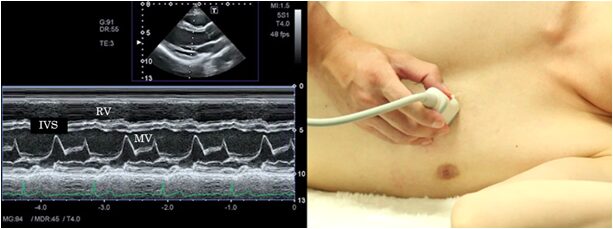

Mitral valve

In M-mode at the mitral valve level, record the parts that ultrasound beam passes through the tip of the cusp of the mitral valve. This view is suitable for observation of the systolic anterior motion of the mitral valve (SAM) seen in hypertrophic cardiomyopathy.